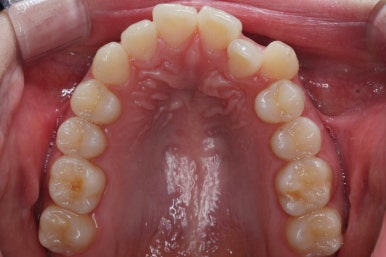

부산부정교합 키다리아저씨치과에 처음 내원하셨을 때의 입안 모습입니다.

위아래 앞니가 삐뚤고 특히 왼쪽 위 송곳니는 밖으로 두드러져 덧니 양상입니다. 윗니는 덧니쪽으로 쏠려 있어서 치열의 중앙이 맞지 않습니다.

전반적인 삐뚤어진 양, 돌출의 느낌, 골격의 비율 등을 고려했을 때 발치 없이 치료를 하기로 했습니다.